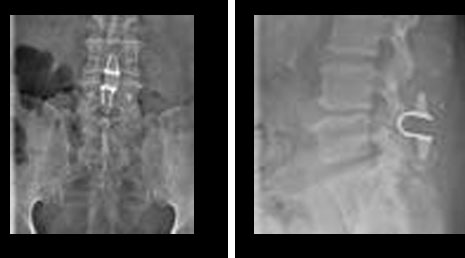

8. Artificial lumbar disc.

38. Lumbar dynamic stablization